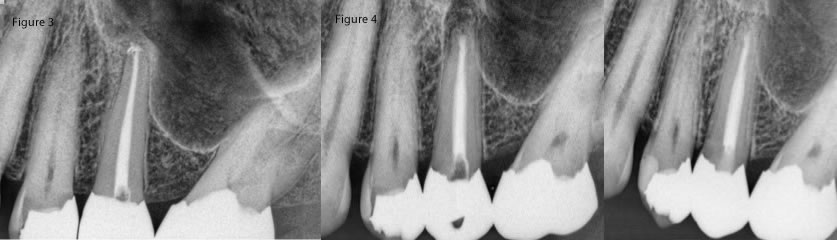

I will say though that while we consider ourselves to be overly safe in our selection process with regards to anatomy, I think that you might be surprised that the treatment is much safer than your original preconceptions. What I mean is that a nearby sinus is not at all an absolute contraindication (figures 1,2,3,4). Additionally, what you might think is too close for a mandibular canal is sometimes not a problem. (figure 5,6,7)

Fig 3: Pre-op #13 near sinus, Fig 4: Immediate post-op #13 and 10 month recall- fistula has not returned.